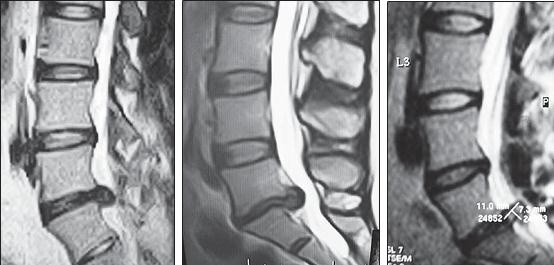

МРТ № 25

На серии снимков МРТ № 25 наблюдаются дорсальные грыжи межпозвонковых дисков в поясничном отделе позвоночника в сегментах LIV-LV Lv—SI Такие комбинации, в которых образуются по нескольку грыж, межпозвонковых дисков одновременно, случаются довольно часто на более поздних стадиях развития дегенеративно-дистрофического процесса. В общем, беда не приходит одна, «несчастье» любит, компанию